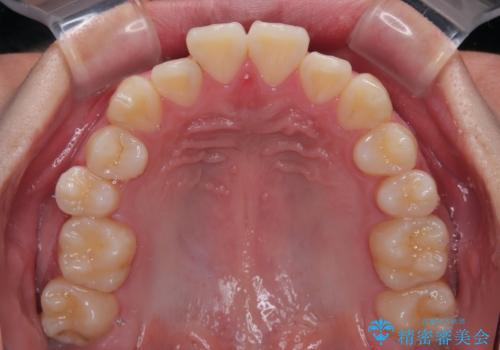

移動が順調に進み、1年半の短期間で治療を終えることができました。

前方に突出した上顎前歯の傾斜も改善されました。